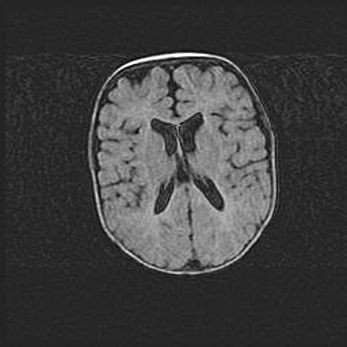

Церебральная ишемия II.

Возраст: 5 дней

Вес: 3400 г

Пол: женский

Окружность головы: 35 см

Срок гестации: 39 недель

Церебральная ишемия – это заболевание, характеризующееся недостаточностью (гипоксией) либо полным прекращением (аноксией) снабжения мозга кислородом по причине закупорки одного или нескольких сосудов. Это приводит к  что метаболическим расстройствам различной степени тяжести в тканях головного мозга, развитию коагуляционных некрозов и гибели нейронов.